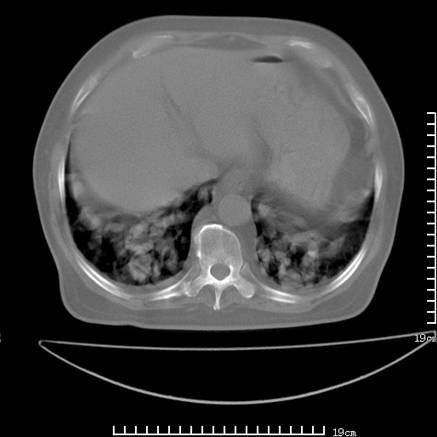

张男,75岁,干咳半年余,小便不利二年,b超检查前列腺增大,未见明显肿块;前列腺癌血生化检查多项指标明显增高。

双肺内多发转移瘤,纵膈淋巴结转移。来源前列腺?建议盆腔mri进一步检查。

双肺转移满了。

两肺广泛转移瘤。